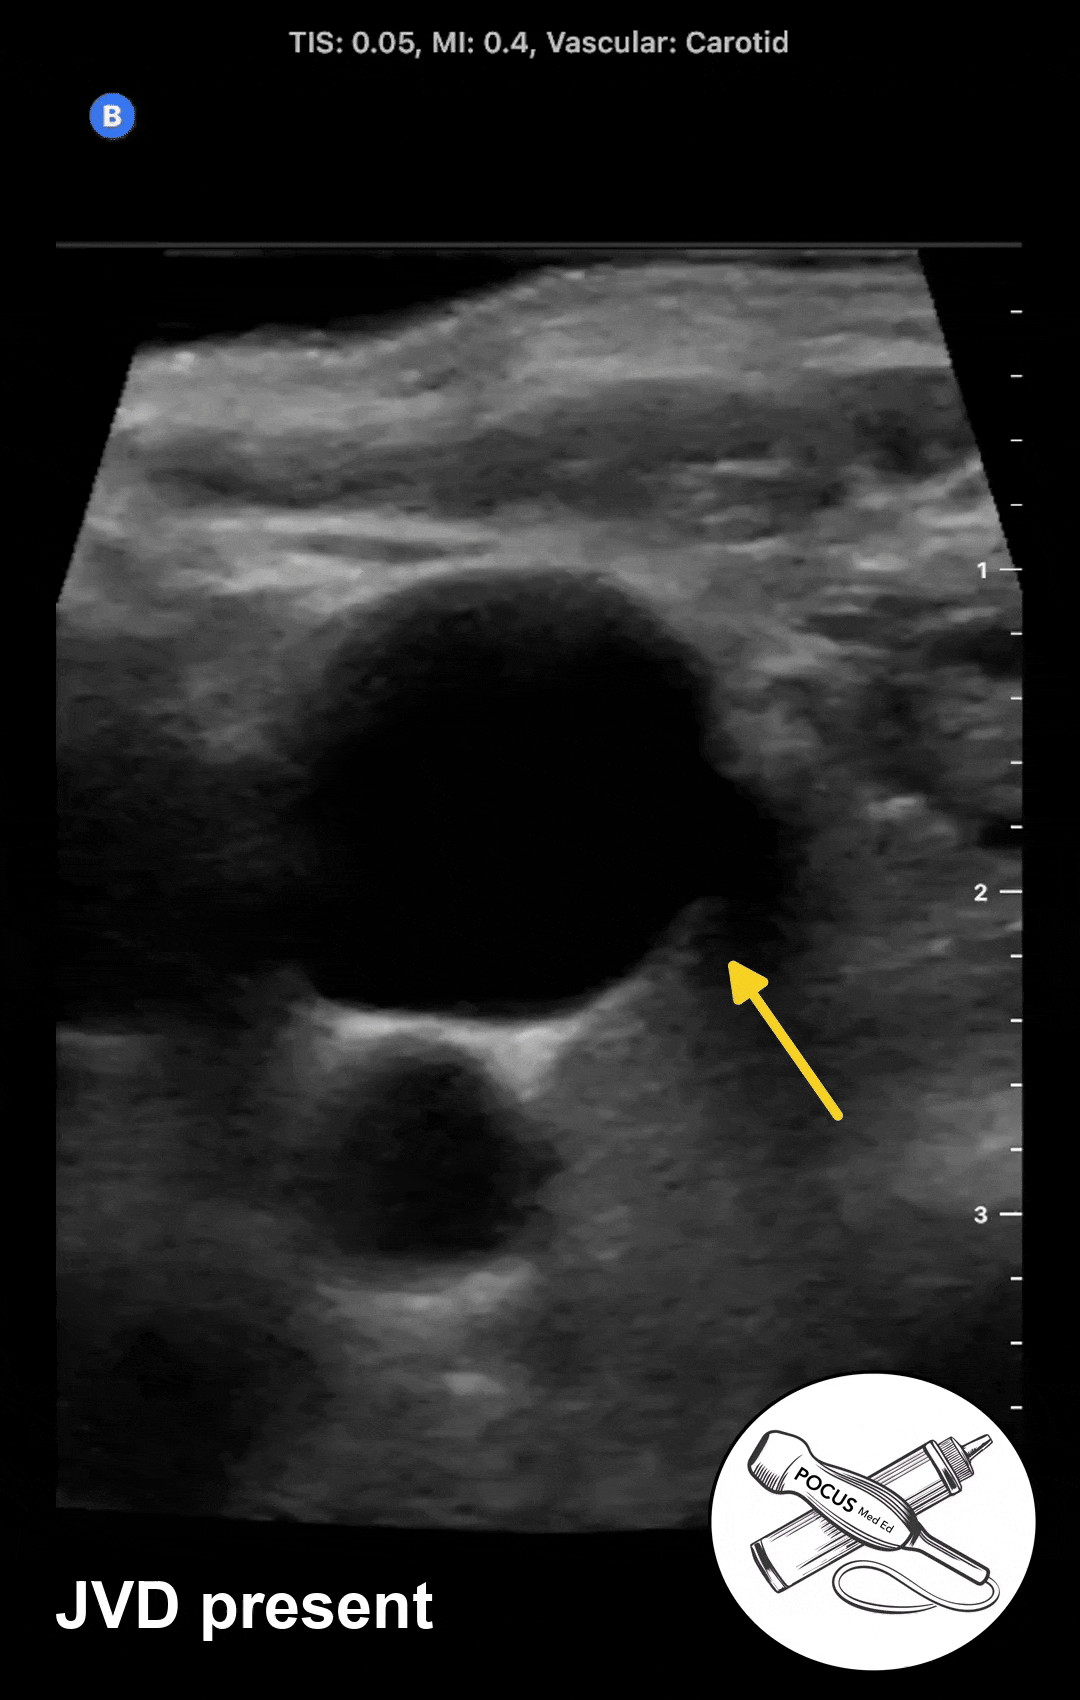

Step 1: Determine if JVD is present

At 45 degrees, in a patient with normal right atrial pressure and no JVD, the jugular vein should be fully or partially collapsed with regular respiration. Most jugular veins sit at the 10 or 12 o'clock position as seen in this example. When JVD is present, the POCUS exam will reveal the jugular vein that is distended without collapse during regular respiration.

If JVD is present, sweep the ultrasound probe up the neck until you find the jugular vein collapse point, where the jugular venous walls are now fully collapsing. This is often absent when right atrial pressure is high, and the collapse point may be above the mandible. Instead of measuring this height with a ruler, a clinician can measure their outstretched fingers as a surrogate to estimate the height. This is the height of the blood column in the visible portion of the vein.